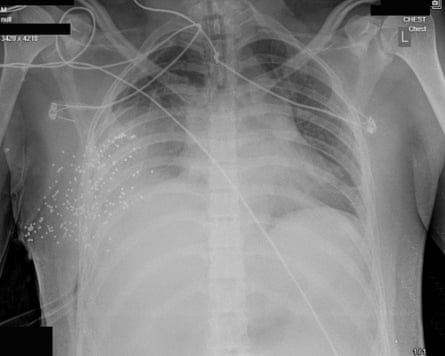

X-rays of the chest of Ali* show more than 174 metal pellets sprayed into his right chest cavity, the metal balls tightly packed, indicating he was shot at extremely close range. His right lung has partially collapsed, and is surrounded by leaking blood and gas. Even with extensive, immediate surgical intervention, his risk of death would be very high, medical experts who have reviewed the images say.

“People think birdshot is less deadly than live ammunition. It’s not,” Haar says. “When you’re firing at point-blank range, all of those metal balls are penetrating – they’re like 100 tiny bullets.”

As well as the violence of the injuries, the X-rays are notable for the patterns they reveal: case after case shows patients shot at short to medium range in the face, chest and genitals.